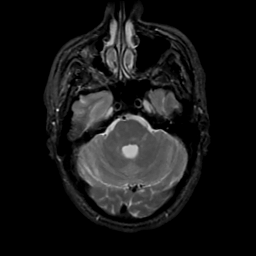

MR Study #4, March 3, 1991 -- Slice #13

[Home][Help][Clinical][Tour 1][Tour 2] Slice 13